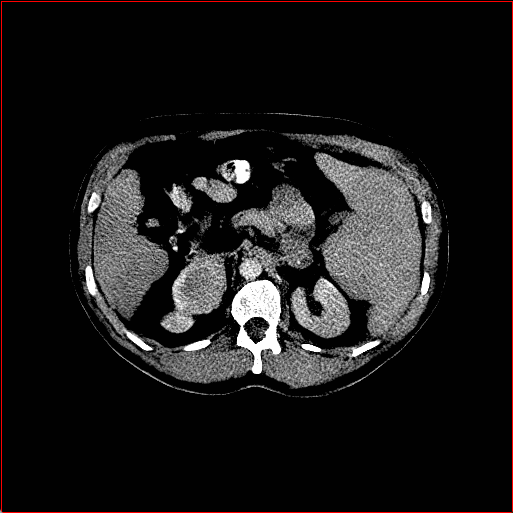

Figure 2: Qualitative comparison across axial (top row), sagittal (middle row), and coronal (bottom row) views. Columns correspond to different methods. MAISI-DDPM and MAISI-v2 in this figure are unconditional synthesis which do not use ControlNet or segmentation maps.

Qualitative Evaluation:

Figure 2 presents representative slices from the axial, sagittal, and coronal planes. GenerateCT (Hamamci et al. 2024) is a 2D model, so it lacks inter-slice consistency, leading to poor image quality in the sagittal and coronal views. MedSyn (Xu et al. 2024) produces noticeably blurry results with mosaic-like artifacts, such as region inside the red box. HA-GAN (Sun et al. 2022) generates visually sharp images but with mosaic-like artifacts, such as region inside the red box. Also, its voxel spacing is not available, which limits its applicability in real-world medical imaging tasks. Moreover, all three methods are restricted to synthesizing small anatomical regions. In contrast, both MAISI and MAISI-v2 are capable of generating high-quality 3D volumes that span larger body regions while preserving fine anatomical details and realistic structure.